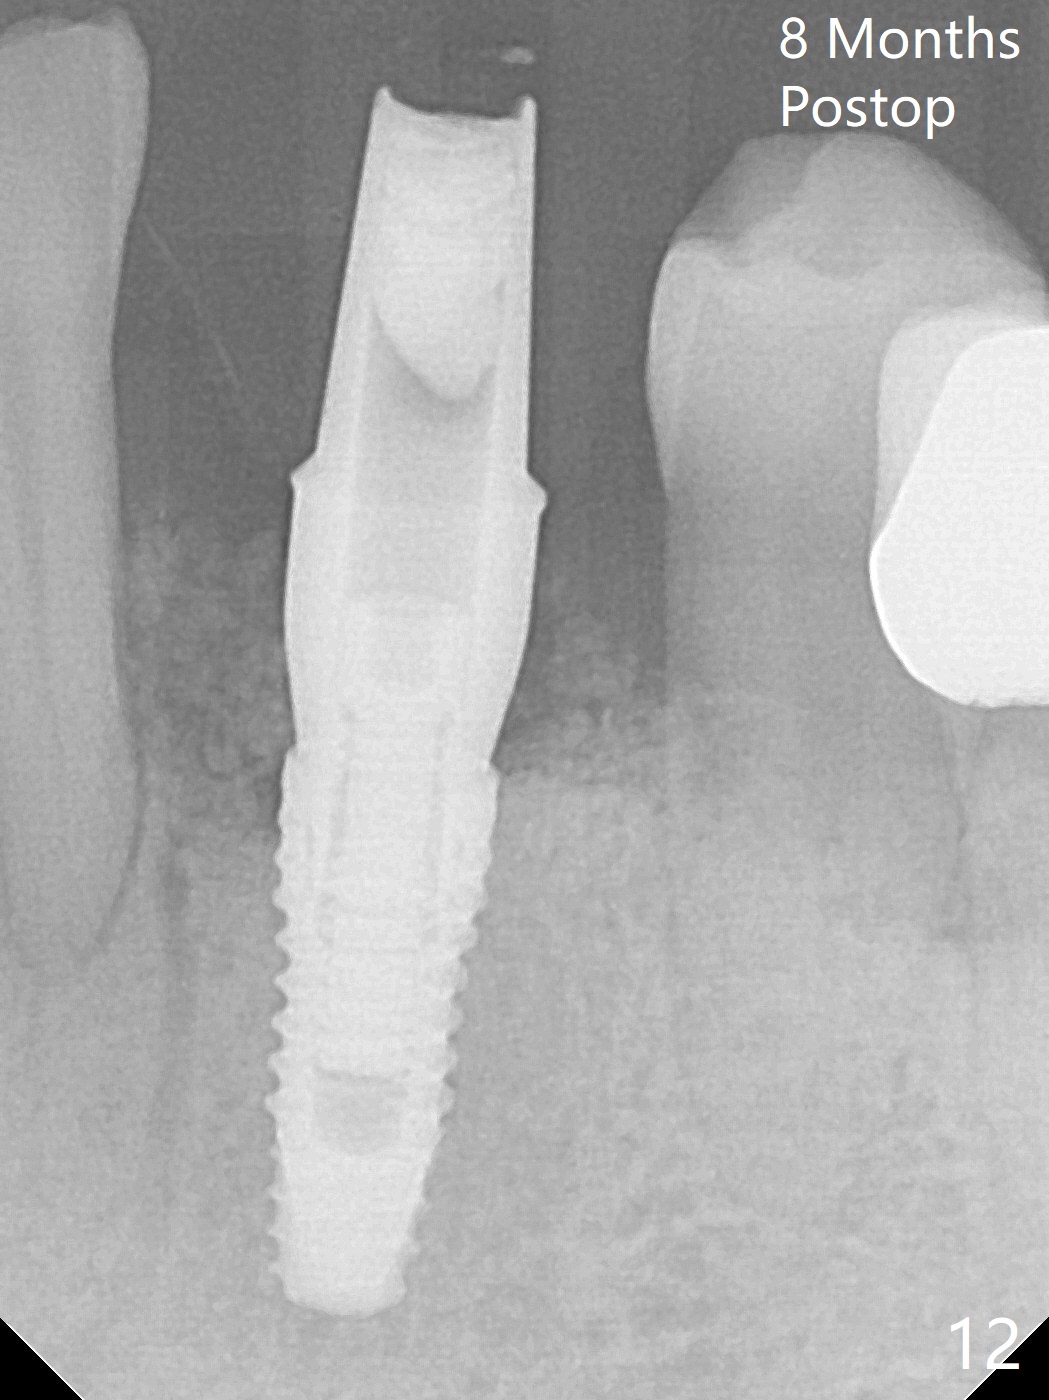

There is a fistula buccal to the apex of the tooth #23 preoperatively (Fig.1), which is related to loss of the buccal plate of the socket of #23. Therefore an implant is placed mainly in the socket of #22 (Fig.3). The lingual (Fig.2 L) gingiva appears to have more extensive inflammation. After extraction, the lingual (Fig.3 L) gingival margin is significantly lower than the buccal one. The lingual crest is ~ 4 mm lower than the buccal one. A 3.8x10 mm dummy implant is placed tentatively with an apical space (Fig.4). When a same dimension definitive implant is placed with 40 Ncm, it is 2 mm below the lingual gingival margin, whereas 6-7 mm below the buccal one (Fig.5). Vanilla graft is placed before placement of a 5.5x4(5) mm abutment (Fig.6,7). There is a 2-3 mm lingual (L) gap to be filled with the allograft secondarily to prevent periimplantitis (Fig.7). Later the abutment is changed to a longer and smaller one (Fig.8) with more of the allograft (*). After trimming of the abutment (Fig.9 (*: papilla between the fused teeth)), an immediate provisional is fabricated to close the socket (Fig.10, similar to Fig.1). The majority of the bone graft seems to be in place 8 months postop (Fig.12). The implant appears to have been placed buccal, consistent with the thin and slightly erythematous buccal gingiva (Fig.13). The ridge completely regenerates 2 years post cementation (Fig.14).